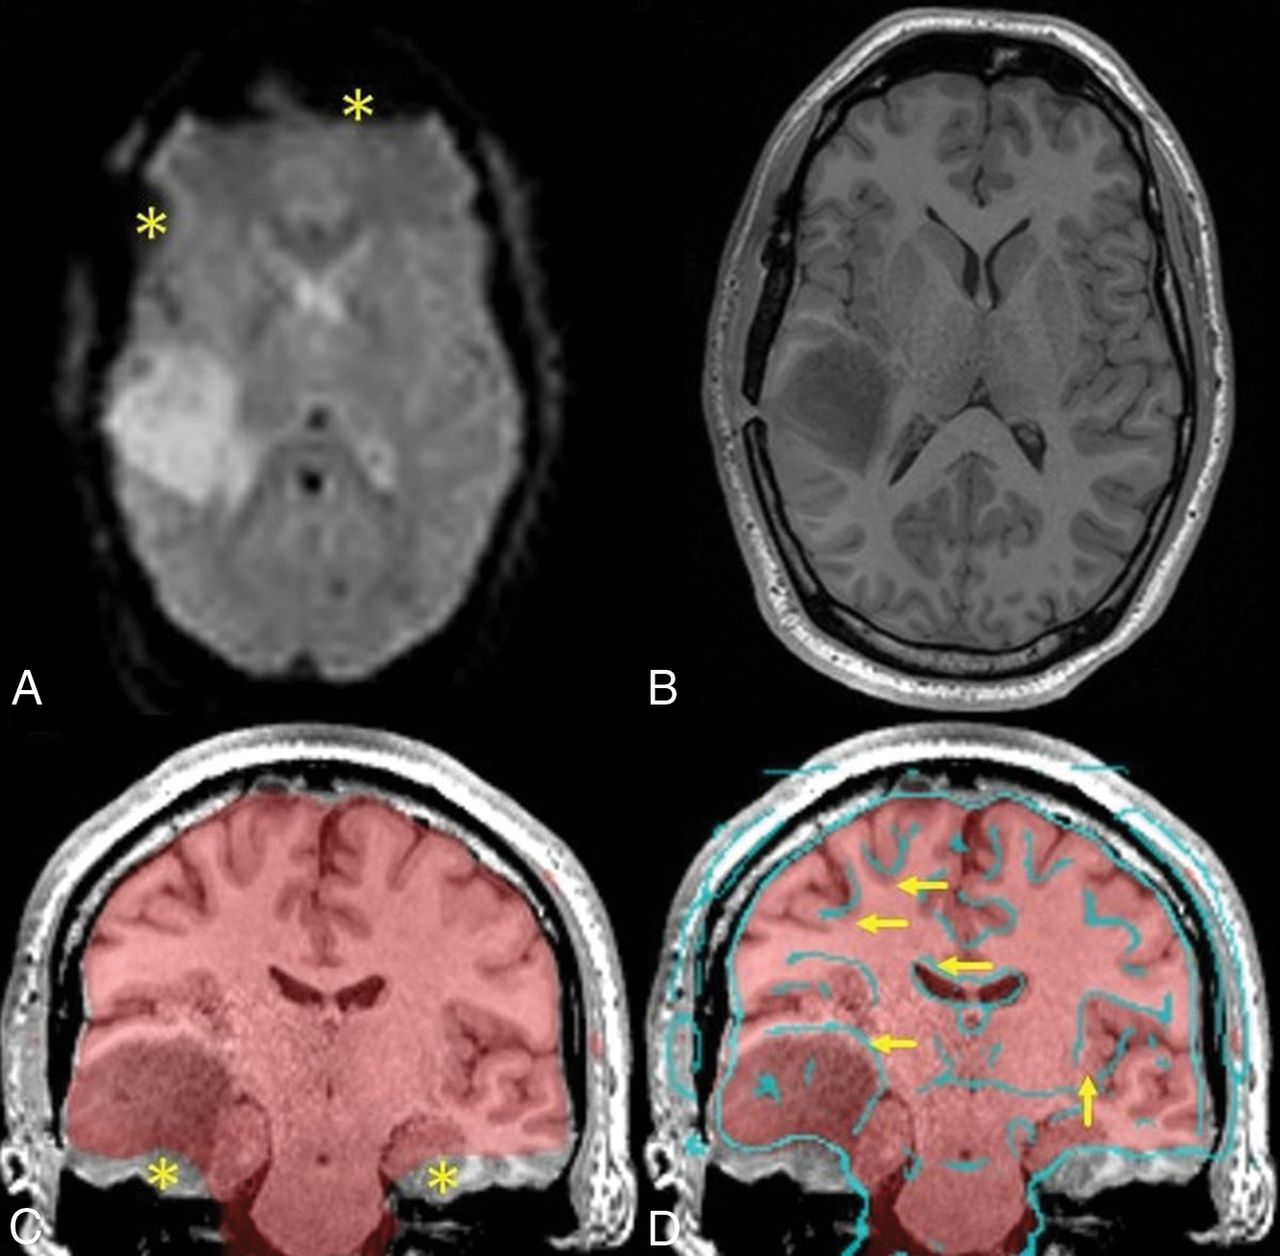

Sample patient with a right temporal lobe tumor. The upper row illustrates the challenge in functional-to-anatomic multimodal alignment between T2* EPI (A) and T1-weighted MPRAGE images (B). Note the inherently poor resolution of EPI. These images also show signal drop-out from susceptibility artifacts near the sinuses and craniotomy (asterisks). The lower row highlights the great difficulty in judging accurate alignment simply by visual inspection. The fusion image of the average EPI mask over the MPRAGE image (C) shows signal drop-out at the skull base (asterisks), which can potentially confound registration algorithms. The fusion image of edge-enhanced EPI (D) delineates structural boundaries in EPI data and reveals slight misalignment (arrows) due to patient motion between MPRAGE and EPI, primarily in the inferior-superior direction along with some rotation.

Interpretation of fMRI depends on accurate functional-to-structural alignment. However, accurate placement of the activation area on the anatomic underlay is fraught with challenges. The images to be superimposed are acquired sequentially, not simultaneously, and patients are not always cooperative in holding still across the entire examination. Registration is then required to account for patient movement by placing the images back into the same reference space. Additionally, the image sequences are multimodal in that the anatomic data are T1-weighted gradient-echo, whereas the functional data are T2*-weighted echo-planar. The latter also has intrinsic geometric distortion with signal drop-out and is typically acquired at a lower resolution (Fig 1, upper row). Functional-to-structural misalignment may be subtle and not easily recognized (Fig 1, lower row). When functional-to-structural misalignment occurs, error is introduced when interpreting the functional significance of apparent gyral activation and when judging lesion-to-activation distances (LADs), which can impact surgical risk assessment.